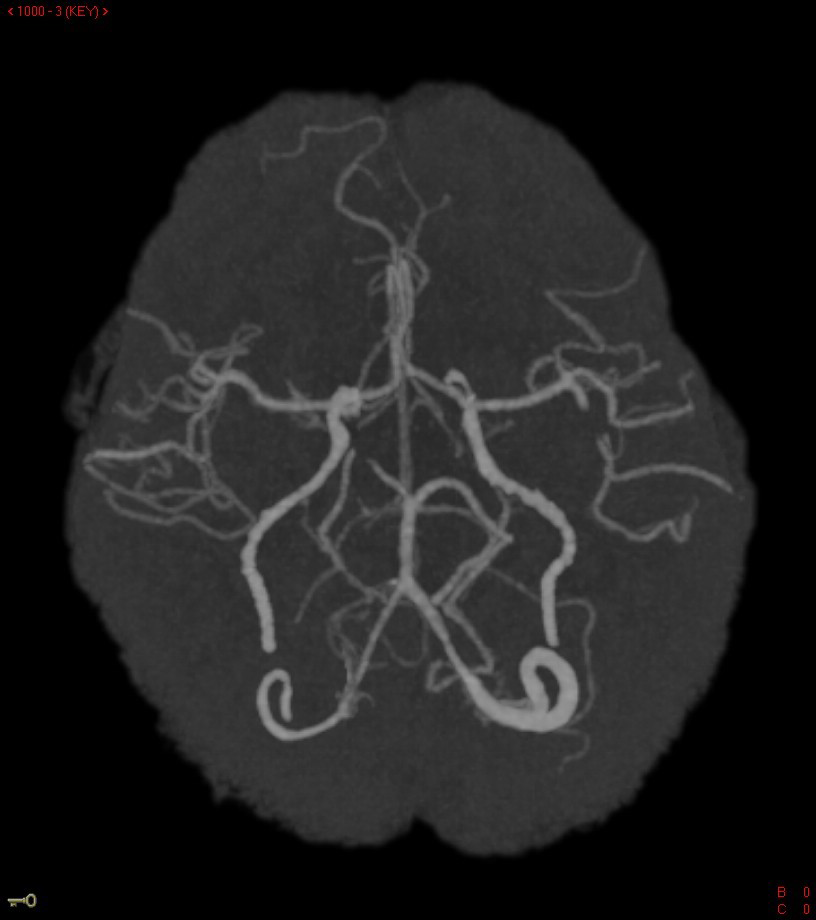

A non-contrast head CT did not demonstrate hemorrhage; however, intravenous rt-PA was held as PTT was elevated at 63 seconds. Further head imaging revealed a 6 mm filling defect in the left M2 branch and a smaller right M3 occlusion (Figure 1). CT Perfusion done at the time demonstrated a moderate left posterior frontoparietal area of perfusion mismatch along with a smaller right frontal area of perfusion mismatch (Figure 2).

Figure 1 Reconstructed images of CT angiogram demonstrating filling defect seen in the left M2 branch of the middle cerebral artery.